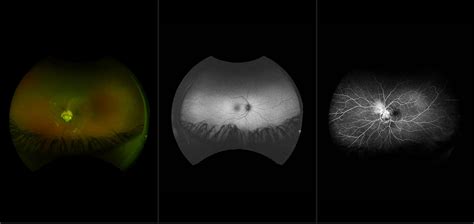

Morning Glory Syndrome, also known as morning glory disc anomaly, is a rare, unilateral—though sometimes bilateral—congenital defect of the optic nerve. It is named for its striking visual resemblance to the morning glory flower. In a healthy eye, the optic nerve head is typically pink, oval, or circular with a clearly defined rim. In contrast, an eye affected by this syndrome presents with an enlarged, excavated, funnel-shaped depression that disrupts the normal anatomy of the optic nerve.

• Excavated optic disc: A deep, white, or yellowish depression at the site where the optic nerve meets the retina.

• Peripapillary halo: A ring of depigmented, raised tissue surrounding the optic nerve head.

• Vascular abnormality: The retinal blood vessels typically emerge from the periphery of the disc rather than the center, appearing straightened and radiating outward like the spokes of a wheel.

• Central glial tuft: A white, grayish mass of tissue often sitting in the center of the excavation.

• Ophthalmoscopy: Direct visualization of the retina to identify the characteristic "flower-like" shape of the disc.

• B-Scan Ultrasonography: Useful for confirming the posterior excavation and ruling out other conditions like staphyloma.